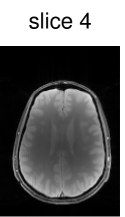

The CAIPIRINHA-based modifications to the SMS pulse design (see Fig. 1(c)) are illustrated in Fig. 5 (showing the case of five slices for the sake of variation). Figure 5(a) shows the unmodified pulse, which differs in structure from the cases with an even number of slices in, e.g., Fig. 4(c) due to the different symmetry of the slice profile (see Fig. 5(b)). On the other hand, the pulse is very similar to the modified pulse for the alternating phase shift; see Fig. 5(c) for the computed pulse and Fig. 5(d) for the resulting slice profile. For illustration, a slice-aliased reconstruction of the acquired in-vivo data using this pulse sequence is shown in Fig. 5(e).

z readout

sG reconstruction

Figure 6 shows the image reconstruction using optimized RF pulses for simultaneous excitation of two, four and six slices with the same slice separation and thickness as above. As can be seen clearly in the first column, all three pulses lead to the desired excitation pattern in-vivo as well. The remaining columns show the slice-GRAPPA reconstructions, which illustrate that the excitation is uniform across the field of view.